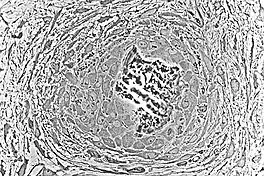

Embryologic mesenchymal cells (MSC) condense into layers of vascularized primitive connective tissue. Certain mesenchymal cells group together, usually near or around blood vessels, and differentiate into osteogenic cells which deposit bone matrix constitutively. These aggregates of bony matrix are called bone spicules. Separate mesenchymal cells differentiate into osteoblasts, which line up along the surface of the spicule and secrete more osteoid, which increases the size of the spicule.

As the spicules continue to grow, they fuse with adjacent spicules and this results in the formation of trabeculae. When osteoblasts become trapped in the matrix they secrete, they differentiate into osteocytes. Osteoblasts continue to line up on the surface which increases the size. As growth continues, trabeculae become interconnected and trabecular bone is formed. The term primary spongiosa is also used to refer to the initial trabecular network.

Osteons are components or principal structures of compact bone. During the formation of bone spicules, cytoplasmic processes from osteoblasts interconnect. This becomes the canaliculi of osteons. Since bone spicules tend to form around blood vessels, the perivascular space is greatly reduced as the bone continues to grow. When replacement to compact bone occurs, this blood vessel becomes the central canal of the osteon.